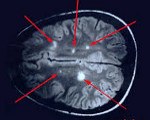

G04 Энцефалит, миелит и энцефаломиелит